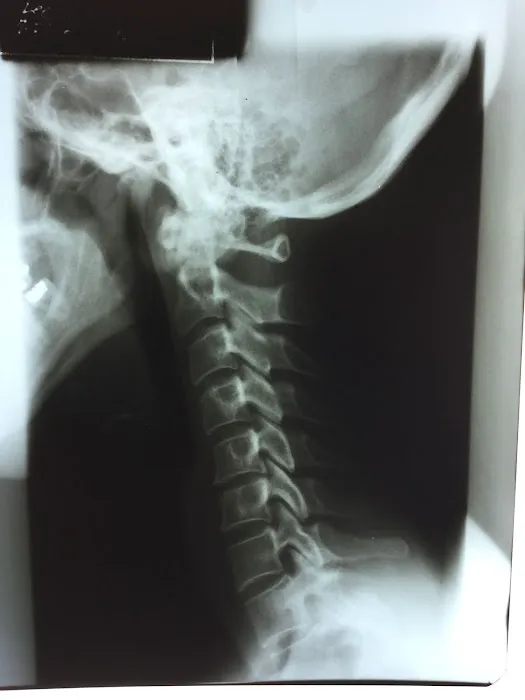

- Cervical Spine Adjustment Specialist